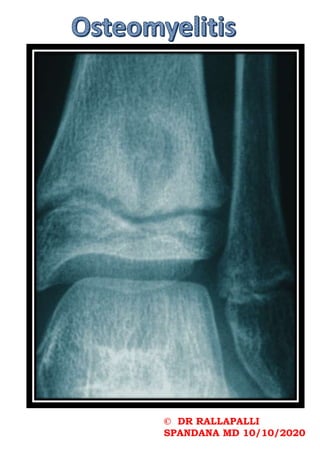

While plain radiographs may show joint

effusions and a loss of soft tissue

planes, there may not be an immediate

indication of bone infection.7 It may

take 10 to 14 days to show 30 to 50

percent of bone mineral loss before

osteomyelitic changes are evident.

A differential diagnosis for

radiographic bony lesions should include

osteomyelitis, leukemia, round cell

carcinomas, Ewing’s sarcoma, metastatic

neuroblastomas, eosinophilic granulomas,

histiocytosis X and tuberculosis.

If radiographs are normal and one

suspects osteomyelitis, proceed to

obtain technetium-99m bone scans.

However, keep in mind that while this

imaging is sensitive for certain bony

conditions, it is not specific.